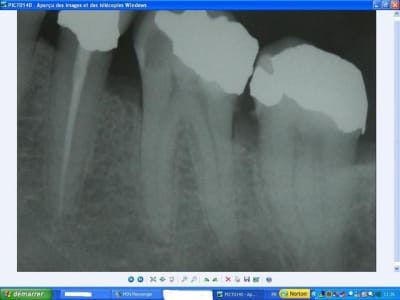

bin c'est beau

sinon, petite reflexion pour le bridge, il semble quand meme avoir été fait rapidement apres l'extraction de la 6 non? l'alvéole semble peu comblée, pour l'inter les rapports avec la muqueuse ça a été au pif?

Une telle image osseuse post extractionnelle ne signifie pas forcément que l'extraction est fraiche. Ca dépend du type osseux et des corticales.

je trouve bizarre la différence entre la première radio,ou tout semble bien aller et les deux autres,ou il y a un problème apparent de cicatrisation,alors qu'elles sont postérieures à la première

problème de contraste de la radio je pense?...